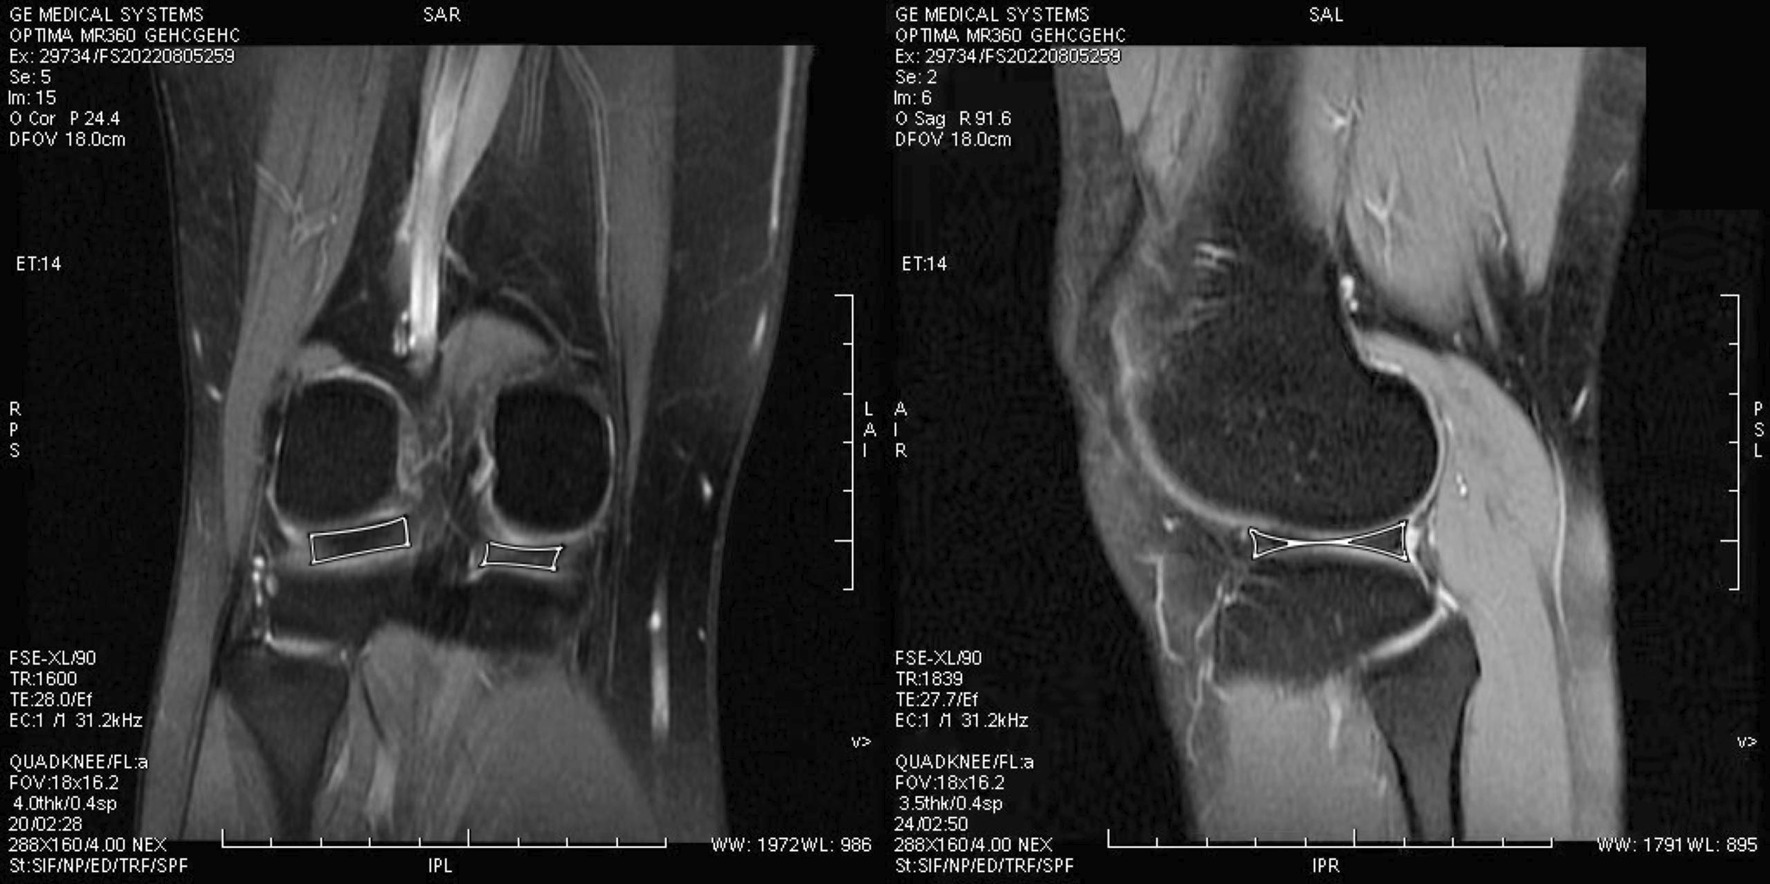

After participants were consented, they were sent to Magnetic resonance imaging room at Beijing Rehabilitation Hospital of Capital Medical University for imaging processing and data measurement. These images were captured and processed by radiologists with at least 10 years above experience in this field. To accurately measure the images, the steps needed to be followed. The first step was to open the TE = 0 images through the three-dimensional synchroview and select the optimal angle to measure the cartilage. Specifically, the signal intensity of cartilage at the thickest bearing point of the medial and lateral femoral condyles, the thickest bearing point of the medial and lateral tibial condyles, the anterior/posterior junction of the femur in the horn of the medial and lateral meniscus, and the anterior/posterior junction of the tibia in the horn of the medial and lateral meniscus were measured. Also, an elliptical region of interest was used to eliminate the errors for measuring the cartilage volume. We calculated the 3D volume of the meniscus base on the reconstruction of sagittal plane image and coronal plane image. Matching the coronal plane image, we operated at the sagittal plane image because the region of interest was easy to fit in (Fig. 2).

Fig. 2.

The coronal plane image and the sagittal plane image of the meniscus